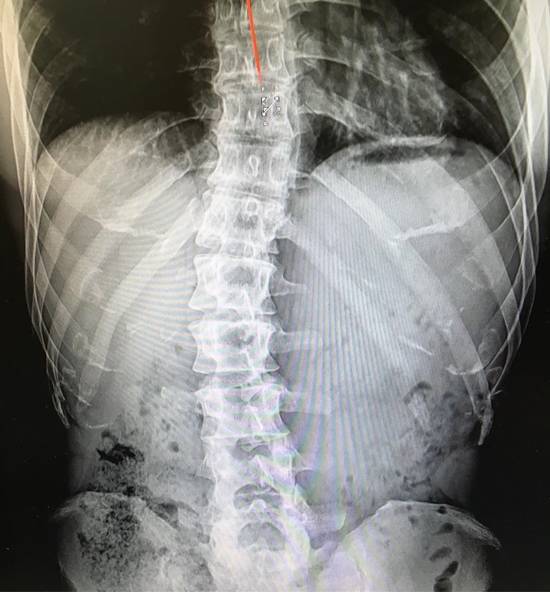

가수 김종국은 4일 자신의 인스타그램에 척추 엑스레이 사진과 함께 척추측만증과 허리 통증을 이겨내기 위해 힘든 시간을 보냈다는 내용의 글을 적었다.

김종국은 "고등학교 때 처음 허리 통증으로 쓰러졌을 때부터 쭉 가지고 있던 척추측만증. '이런 허리로 어떻게 그런 몸을 만들죠?' 한다. 난 만들었다. 아니 만들고 있다. 이 휘어진 척추를 뭔가로 잡아줘야하니까"라고 자신이 운동을 시작하게 된 계기를 말했다.

이어서 "나약한 인간들이 불가능이라고 입으로만 떠들고 온갖 핑계 삼아 술 먹고 놀러 다니고 따뜻한 이불 속에서 편하게 쉴 때 난 이 악물고 잠 줄이고 이러고 산다"면서 "제발 '저게 말이 돼? 분명 이럴거야' 이것 좀 하지 말고 살자. 자신이 못한다고 단정짓고 해낸 사람을 오히려 폄하해야 위로가 된다는 거 알고는 있는데 이제라도 본인이 진짜 못할 거라고 믿고 산거 지금 하나라도 시작해보자"고 자신의 노력을 오해하는 사람들에게 일침을 가했다.